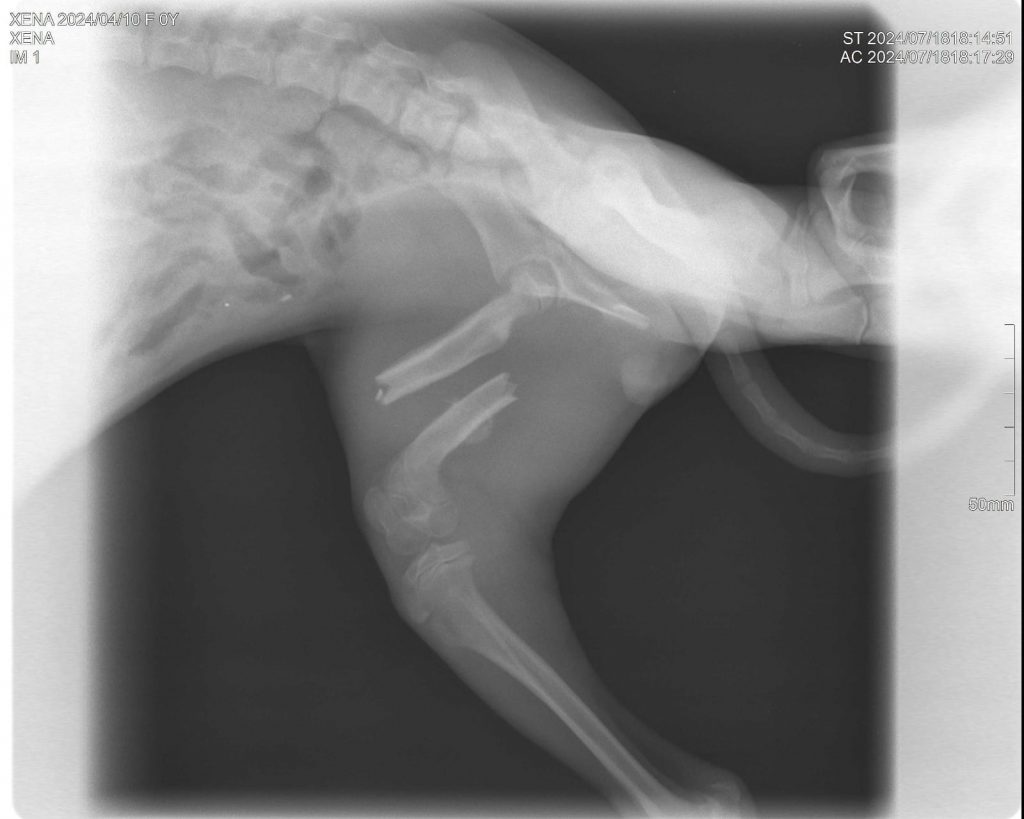

Nous avons fait connaissance avec toute la troupe des 4 pattes, les malades et les cassés physiquement et moralement. La veille Loli avait récupéré une baby podenca avec une patte arrière cassée, son propriétaire l’avait déposée a la clinique pour une euthanasie, elle a été baptisée Lotta et sera opérée mardi pour lui poser une plaque,